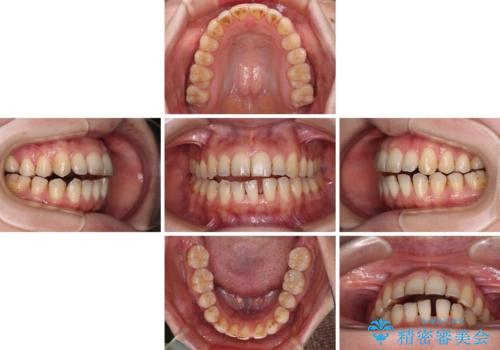

クロスバイトはワイヤー矯正が得意とするところであり、上下前歯の非接触や開咬はインビザラインの得意とするところであるので、ワイヤー装置により事前にクロスバイトを改善し、その後にインビザラインにて仕上げていくこととしました。

奥歯の咬み合わせに問題がある場合、インビザラインでは改善できないことが多々あります。事前にワイヤー装置により問題点を解消しておくことで、スムーズにインビザラインでの矯正治療を進めていくことができます。